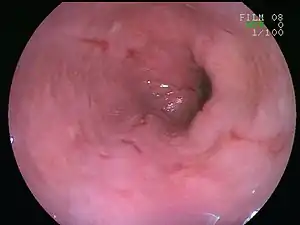

![]() | |

| An esophageal ulcer visualized by esophagoscopy: the reddened area at 10 o'clock on the surface of the mucosa. | |

Esophagitis can be diagnosed by upper endoscopy, biopsy, upper GI series (or barium swallow), and laboratory tests.[4]

An upper endoscopy is a procedure to look at the esophagus by using an endoscope. While looking at the esophagus, the doctor is able to take a small biopsy. The biopsy can be used to confirm inflammation of the esophagus.